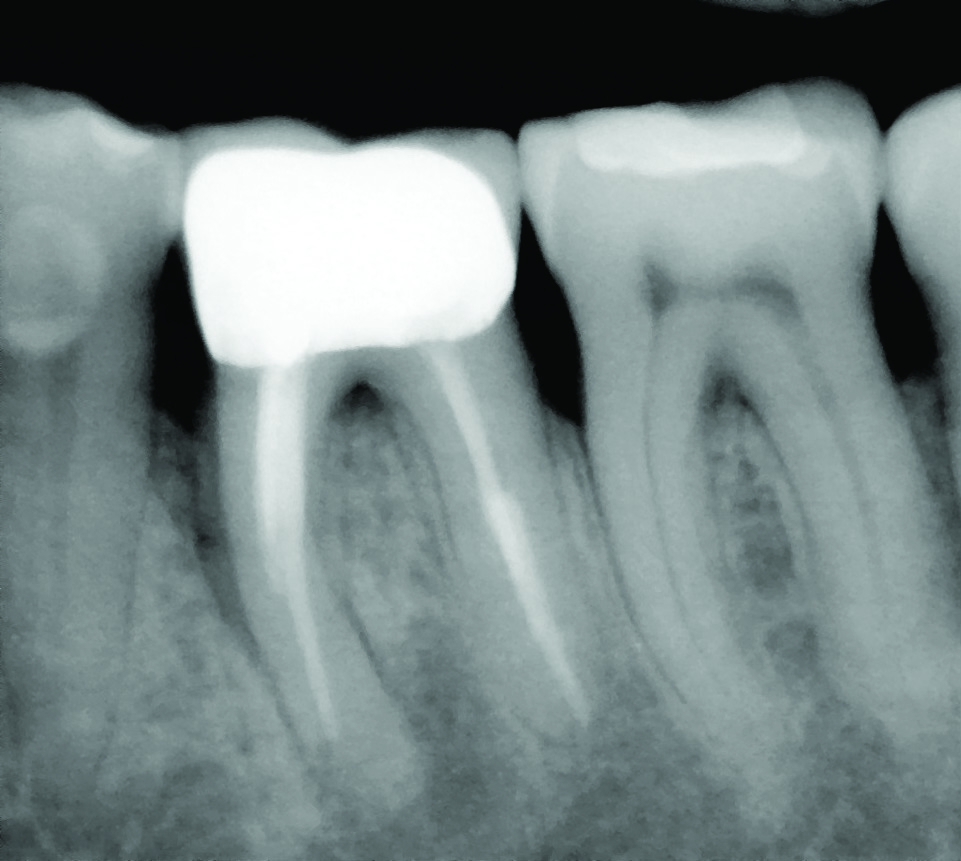

Fig 2. Examples of multirooted teeth showing periradicular periodontitis and loss of periradicular bone support isolated to one root (indicated by red arrows). Fig 1: Tooth No. 3 distobuccal root with circumferential bone loss from the crestal bone height to the apex with stable mesiobuccal and palatal roots. Fig 2: Tooth No. 30 with a prior apical surgery showing bone loss surrounding a fractured mesial root. Fig 3: Tooth No. 19 with lateral and apical bone loss regions affecting a fractured mesial root. Fig 4: 3D CBCT imaging of tooth No. 3 depicting an apicomarginal bone loss defect affecting the mesiobuccal root with stable fused distobuccal and palatal roots.

Fig 1 through Fig 4. Examples of multirooted teeth showing periradicular periodontitis and loss of periradicular bone support isolated to one root (indicated by red arrows). Fig 1: Tooth No. 3 distobuccal root with circumferential bone loss from the crestal bone height to the apex with stable mesiobuccal and palatal roots. Fig 2: Tooth No. 30 with a prior apical surgery showing bone loss surrounding a fractured mesial root. Fig 3: Tooth No. 19 with lateral and apical bone loss regions affecting a fractured mesial root. Fig 4: 3D CBCT imaging of tooth No. 3 depicting an apicomarginal bone loss defect affecting the mesiobuccal root with stable fused distobuccal and palatal roots.

Fig 5. A cleansable resected root surface, the root filling, and the root contour will affect the prognosis. Fig 5: Tooth No. 19 at 1-year post-treatment with a remaining stub of the mesial root following root resection; note a subsequent larger-than-expected crestal bone loss defect below the cantilevered portion of the tooth. Incomplete resection and lack of proper contour toward the mesial contact has created a plaque trap and subsequent unstable periodontal status. This problem can be avoided with a more aggressive resection to ensure a cleansable situation. Fig 6: Clinical image of tooth No. 14 with a resected mesiobuccal root and RMGI restoration of the underside of the tooth. The resultant contour has no lips or ridges and has a smooth transition to the mesial contact space; there is also a smooth transition to the remaining distobuccal and palatal roots, creating a cleansable situation. Fig 7: Tooth No. 18 immediately following resection of the mesial root demonstrates a contoured mesial surface that smoothly blends to the mesial contact region. The underside of the cantilevered portion of the tooth is restored with a RMGI restoration, and the socket is grafted with an allograft.

Fig 8: Tooth No. 30 with a resected mesial root and restoration of the underside with a RMGI restoration at 5 years post-treatment is displaying the expected healing pattern of the crestal bone following grafting of the socket. The proper resection and contouring permits adequate maintenance and resultant stability of the tooth.